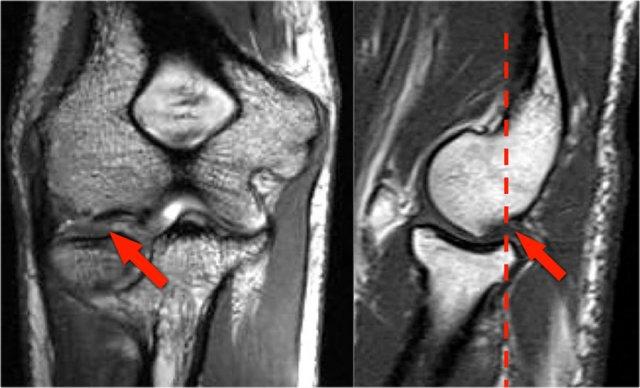

Trên các hình ảnh mặt phẳng coronal, bó trước của dây chằng UCL hiện rõ đẹp, nhưng lưu ý rằng có sự hình thành gai xương ở phần trong của khớp (mũi tên đỏ).

Khi chúng ta đi xa hơn về phía sau có một vùng nhỏ có tín hiệu thấp (mũi tên vàng), đây là một chỗ bong gân của một phần dây chằng bên trụ (UCL).

Điều này được thể hiện rõ hơn trên phim X-quang.

Continue with the axial scan.

Khi quan sát trên lát cắt ngang (axial), chúng ta có thể nhận thấy sự hình thành gai xương khổng lồ.

Lưu ý rằng dây thần kinh trụ (mũi tên màu xanh) nằm cạnh các gai xương này và những bệnh nhân này có thể biểu hiện bệnh lý thần kinh trụ.